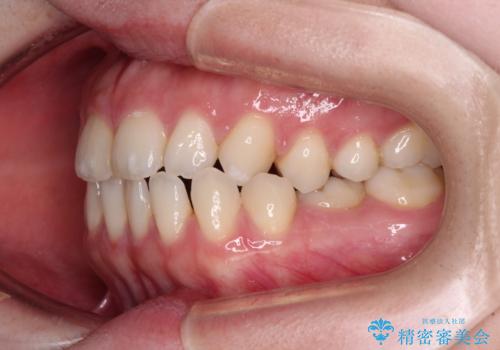

すきっ歯をインビザラインできれいな歯並びに改善

- 前歯の隙間を気にして来院された患者様です。

隙間や叢生の程度はそれほど著しいものではなかったので、インビザラインでもワイヤー矯正でも対応可能でしたが、極力目立たない装置を希望されたため、インビザラインにて矯正治療を行うこととしました。

すきっ歯の原因は色々ありますが、嚥下や発音時の舌突出癖が大きな原因となることがあります。

こちらの患者様も強い突出癖があったため、舌のトレーニング指導を行いました。